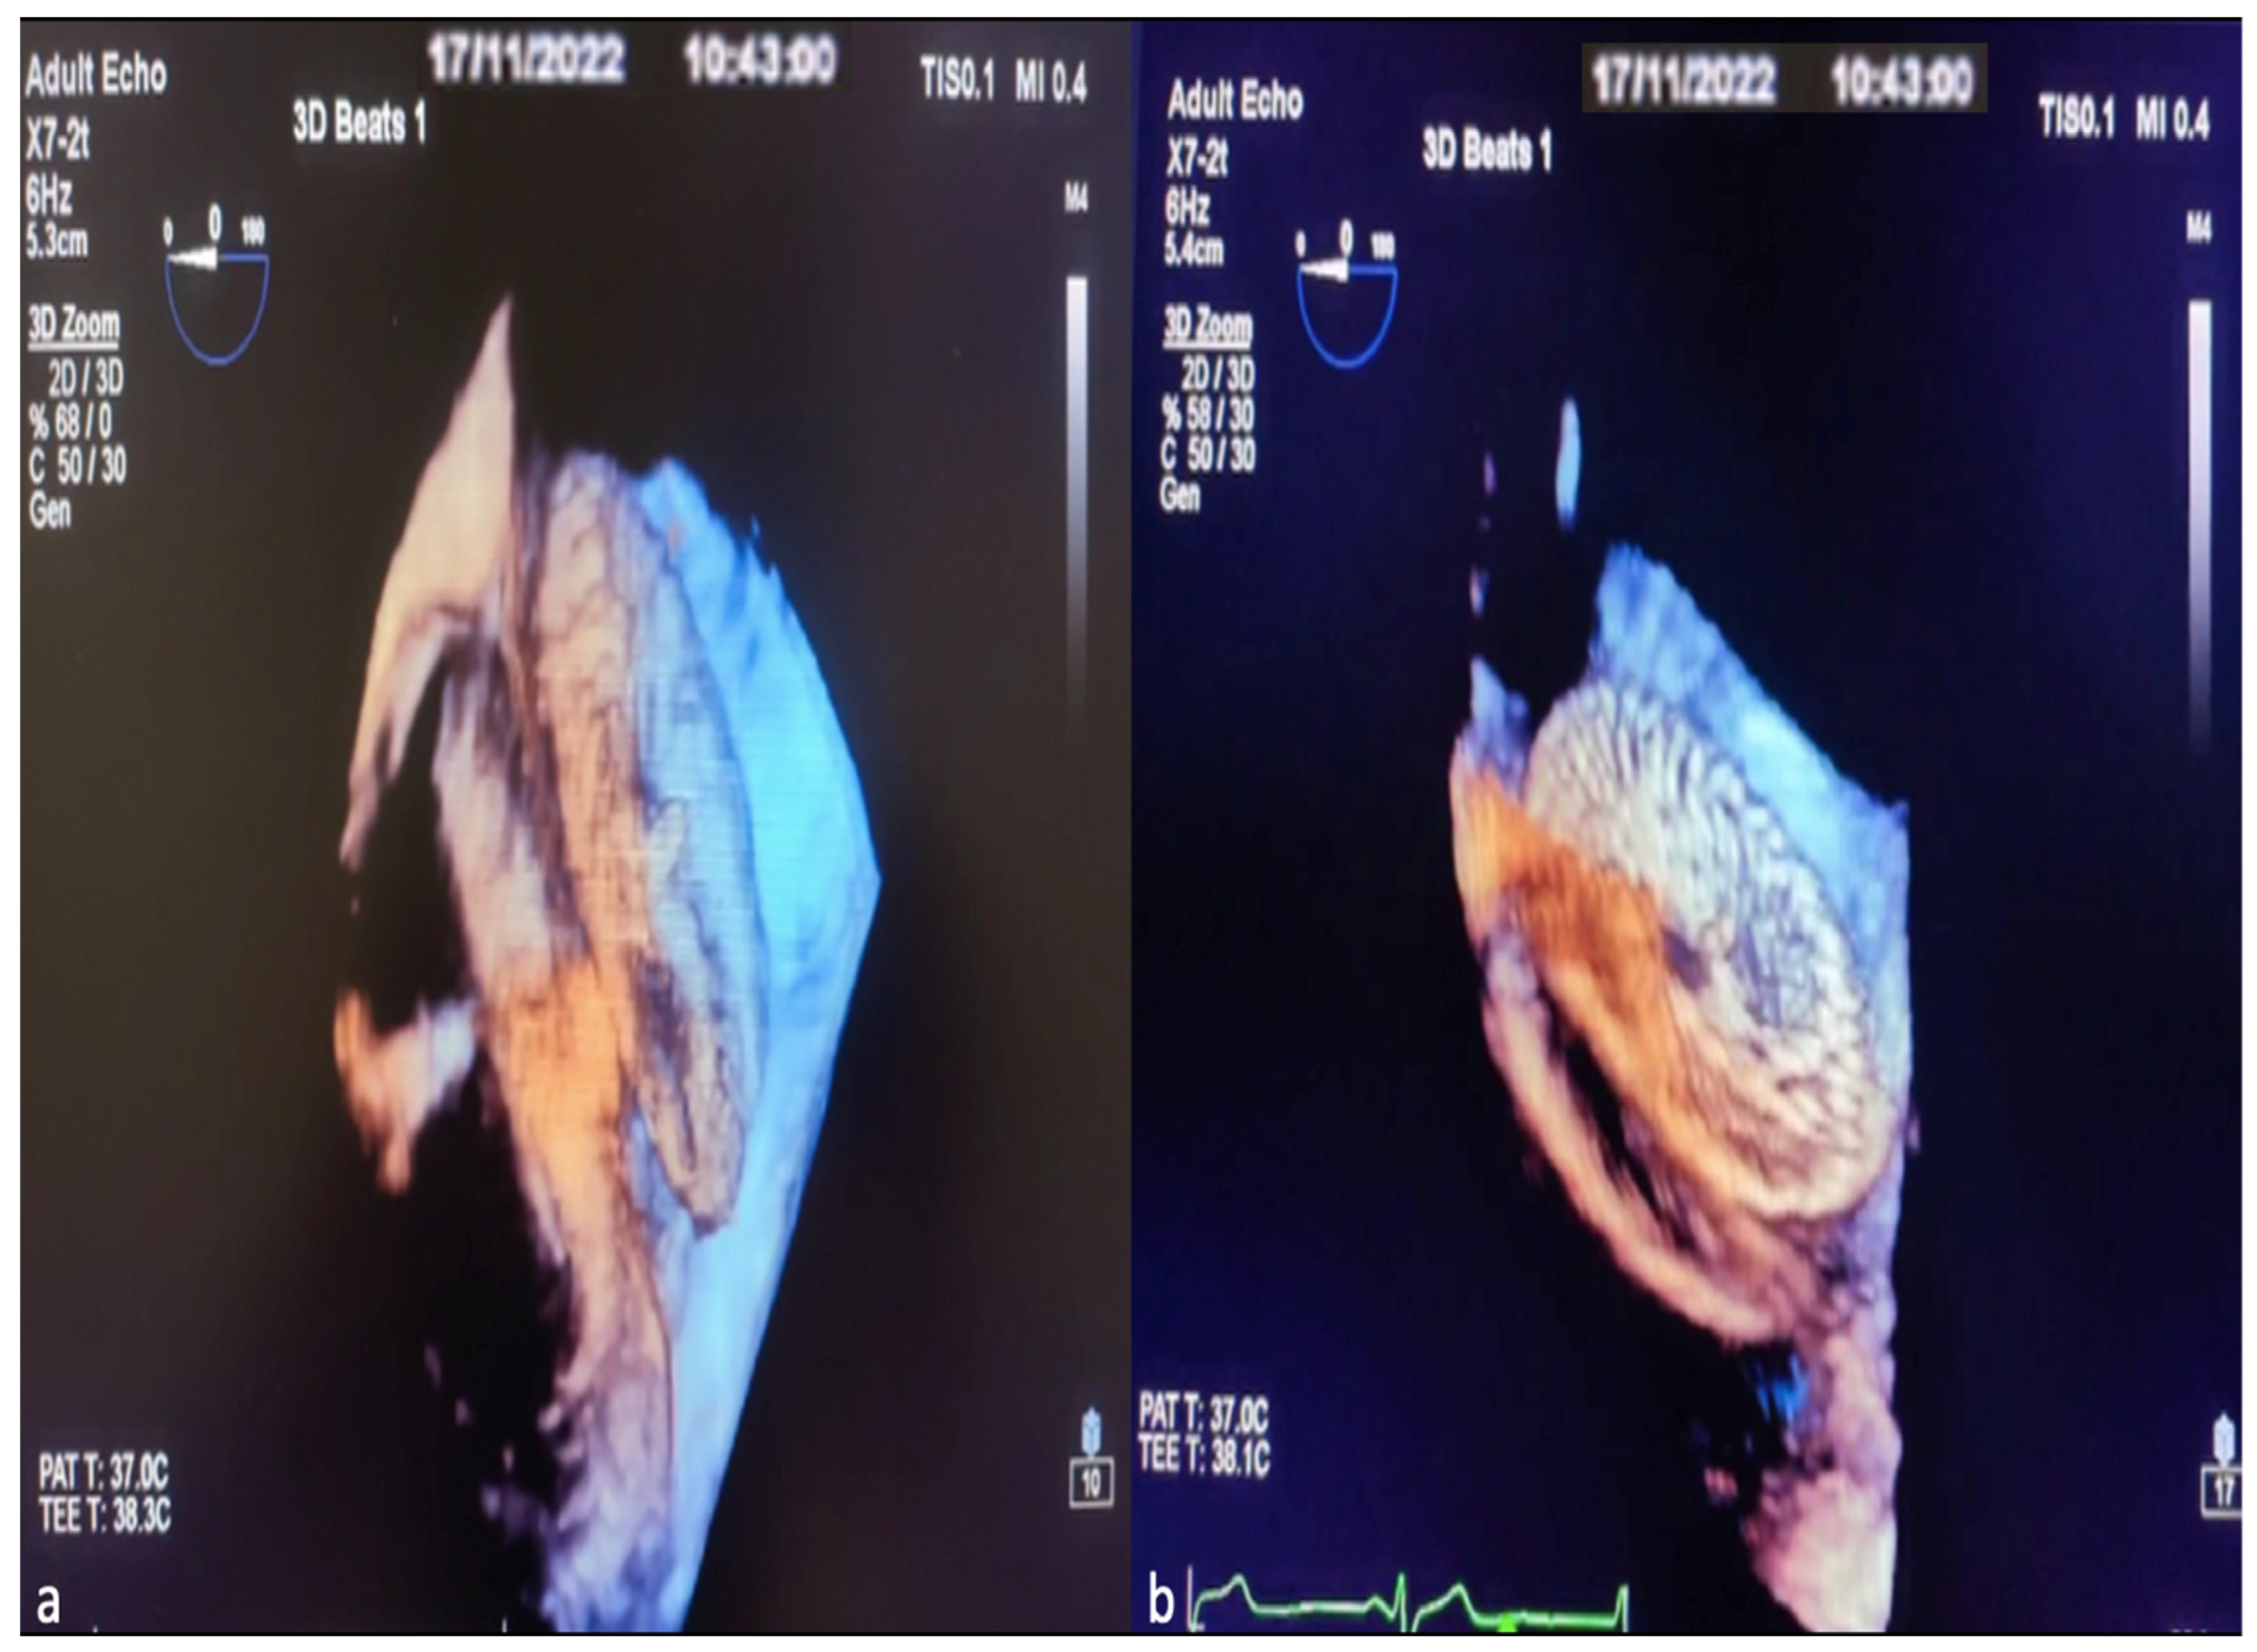

Finally, after observing that the device was in the appropriate position and place, the stability of the device and the rims were checked with the Minnesota maneuver (the device is moved back and forth with the help of the catheter). Once the optimal implantation was determined, the device was released, and the procedure was completed. The 3D TEE image of the ASD occlusion device before release and after release is shown in Figure 5a,b.

Figure 5. Images of ASD occlusion device closure with intraoperative 3D TEE procedure. View the implanted device from the lateral interatrial septum before it is separated from the delivery system (a). Image of the ASD occlusion device after leaving the delivery system (b).